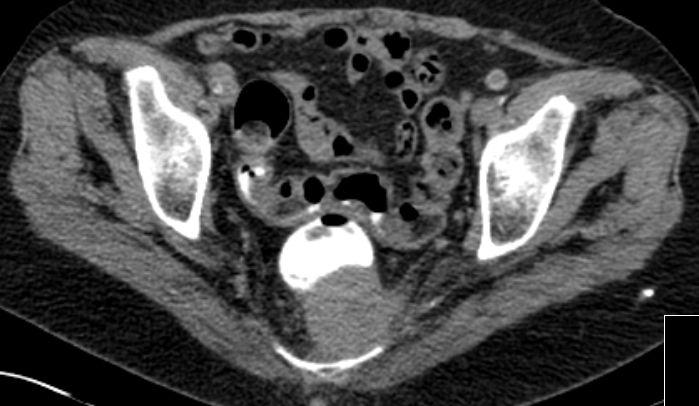

| Rektum | 70-jährige Frau mit Verdacht auf Rektumkarzinom. Histologische Plattenepithekarzinom.![]() | ||

![]() |

![]() | ||